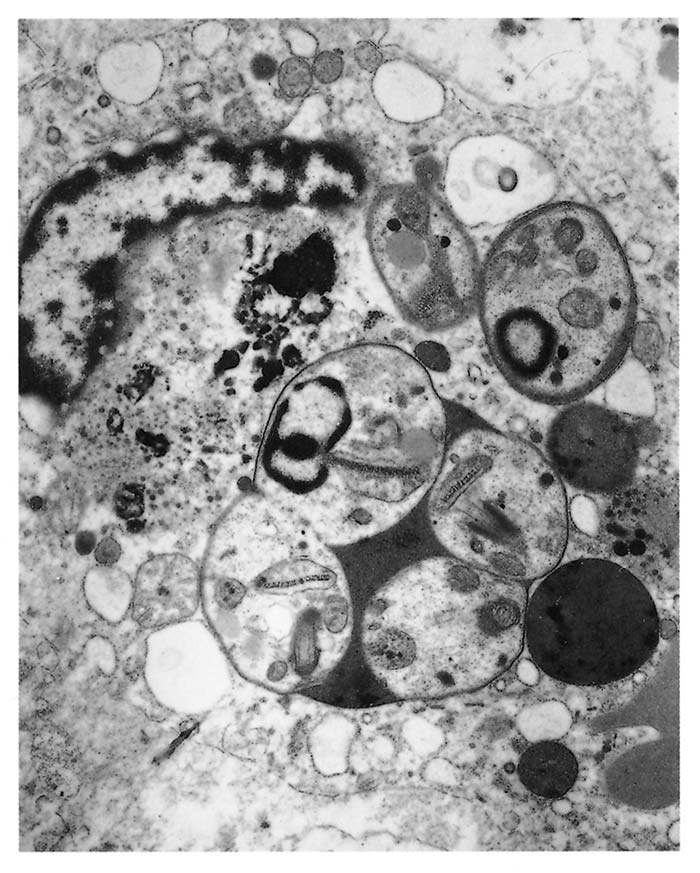

The parasite occurs in two forms: a promastigote stage which is found in the sandfly; and an amastigote stage which occurs in the mammalian host. During feeding, the infected sandfly injects promastigotes into the dermis of the mammalian host and these are engulfed by phagocytic cells before transforming into amastigotes which multiply by binary fission. Heavily parasitized host cells eventually rupture, and the liberated amastigotes invade other macrophages in which they may be spread locally or systemically.17 In tissues, amastigotes of all Leishmania spp. are morphologically similar (Figure 22.2 and Figure 22.3): they are round to oval bodies, 1,5–3 × 2,5–6,5 μm in diameter, containing a single nucleus and a rod-shaped kinetoplast.17